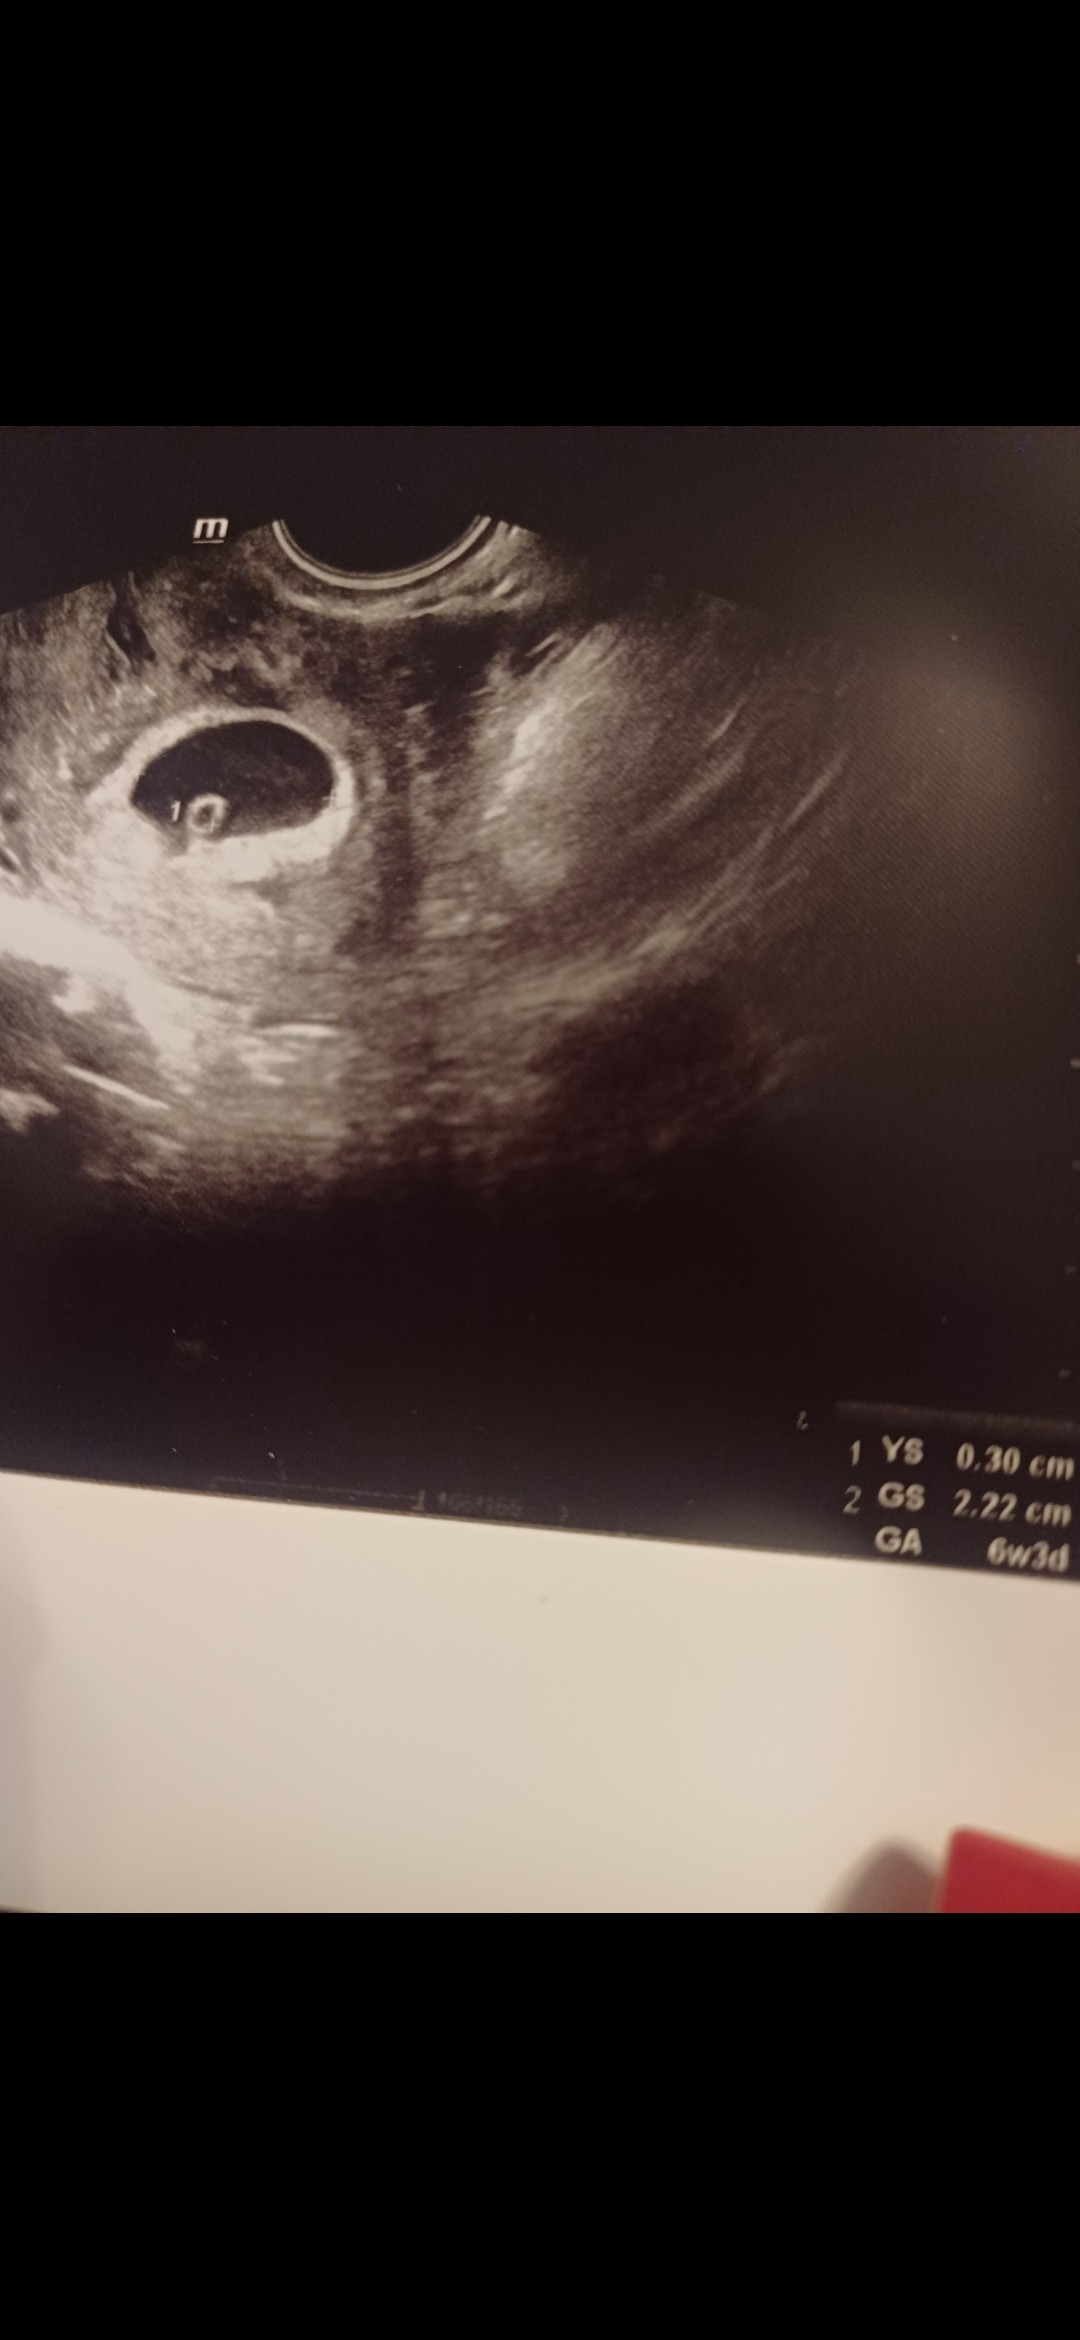

Hejka, ja po wizycie. Jest zarodek i serduszko. Termin mam na dzień mamy

Dziś 6t3d. Więc pewnie rozpakuje się na końcu bo córkę miałam porod wywoływany w 41 tygodniu 😅